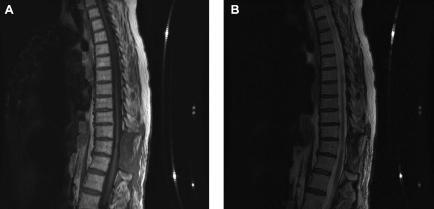

We present a case of an intramedullary melanotic schwannoma (IMS) of the thoracic spinal cord. To our knowledge, this is the seventh reported case of an IMS of the central nervous system. Schwannomas are benign nerve sheath tumors of neural crest origin composed entirely of well differentiated Schwann cells that typically occur in peripheral nerves. Both the intramedullary location and the melanotic component of the reported lesion make it exceedingly rare. We will present our case, theories as to the origin of these tumors, clues in radiographic identification, and current clinical follow-up recommendations.

我们报告一例胸段脊髓髓内黑色素性神经鞘瘤(IMS)。据我们所知,这是中枢神经系统IMS报告的第七例。神经鞘瘤是起源于神经嵴的良性神经鞘肿瘤,完全由分化良好的施万细胞组成,通常发生于周围神经。所报告病变的髓内位置和黑色素成分使其极为罕见。我们将展示我们的病例、这些肿瘤的起源理论、影像学识别线索以及当前的临床随访建议。